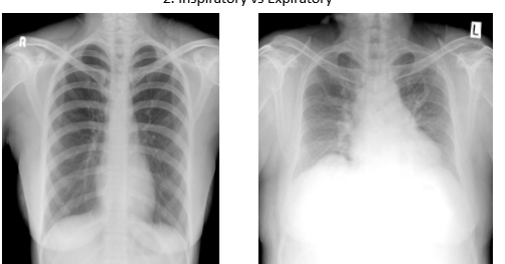

which is inspiration vs expiration. how do u know?

Pic 1: inspiration (inhale —> diaphragm goes down. you can see 9-10 ribs in full inspiration)

u want pt in full inspiration to see how much air lungs can hold. u want to see if there are issues w lung getting air

Pic 2 expiration: u see less than 9 ribs